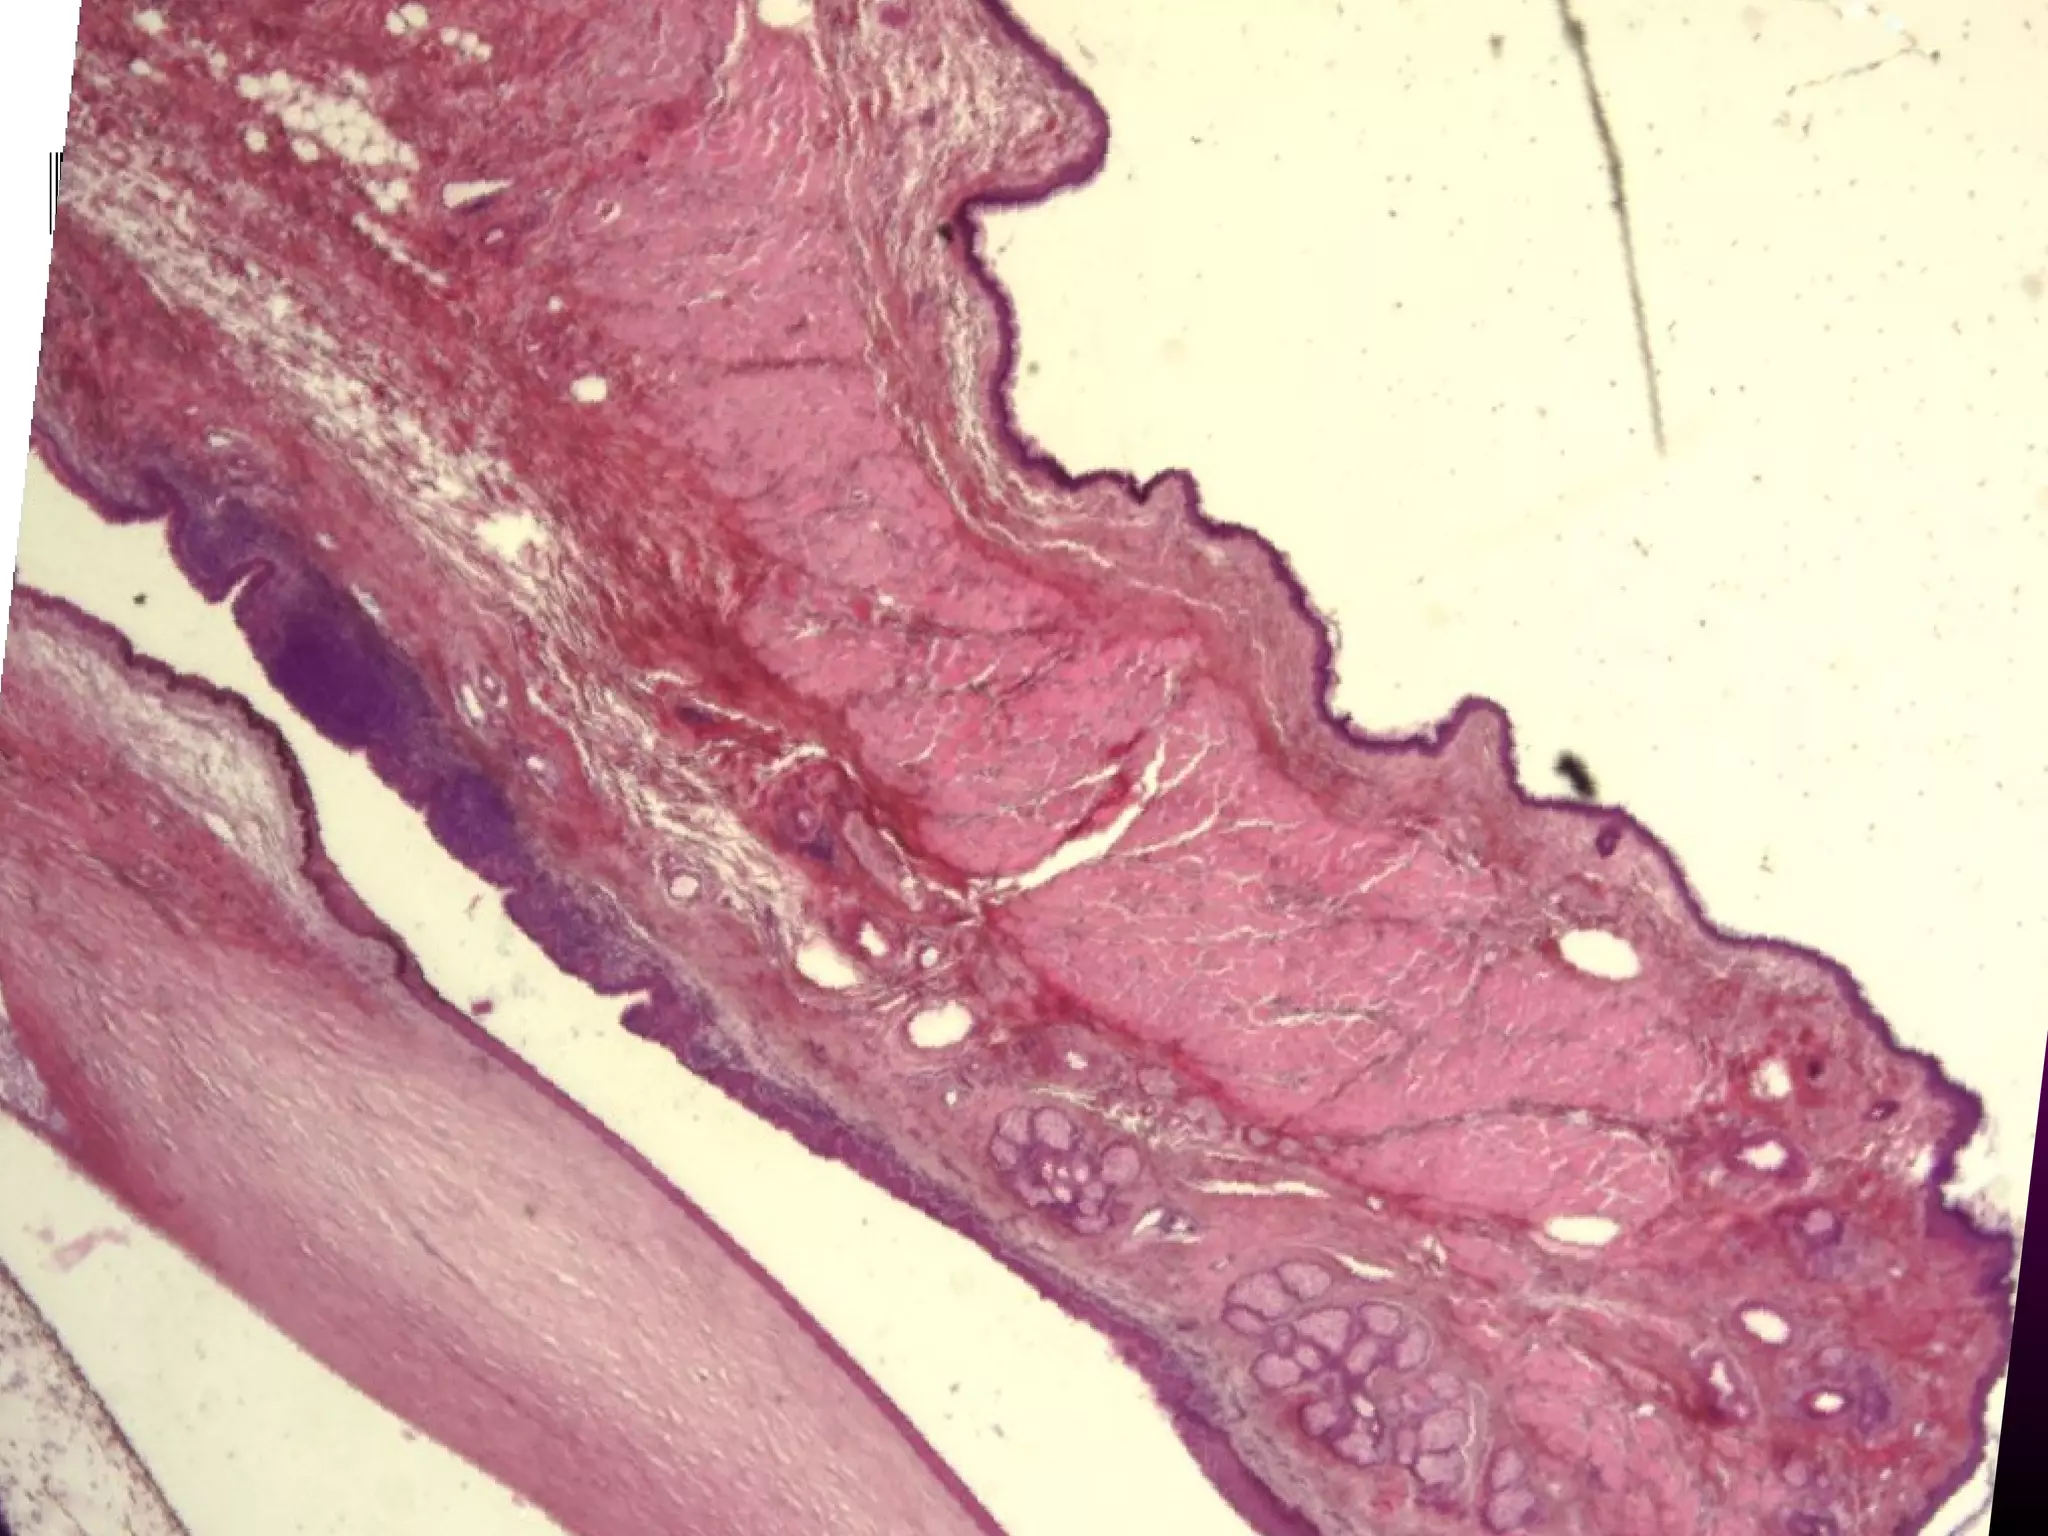

• #39 Perimysium - coverage of a groups of muscle fibers with connective tissue Coverage of the entire muscle is by another connective tissue sheath the epimysium which merges with tenon’s capsule.